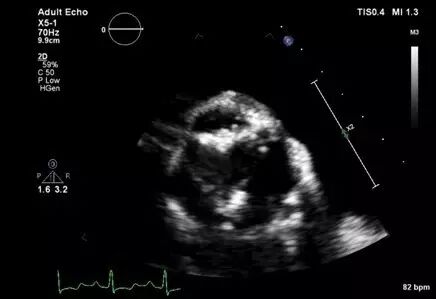

图2 四腔切面显示,二尖瓣重度增厚特征